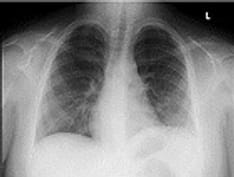

A 54-year-old patient developed cough with foul-smelling sputum production. A chest radiograph shows lung abscess in the left lower lobe, superior segment.

A 42-year-old man developed fever and production of foul-smelling sputum. He had a history of heavy alcohol use, and poor dentition was obvious on physical examination. Chest radiograph shows lung abscess in the posterior segment of the right upper lobe.